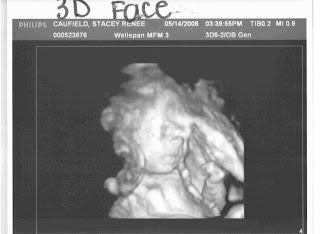

We had another doctors appointment this evening. Before we went to the doctors we got a 4D ultrasound. Everything looked great and we even got a video of the ultrasound. Mike tried to burn the dvd but for some reason it wouldn't burn correctly so we won't be able to send out an dvd's. Everyone will have to come and visit if you want to see the video. The little guy wasn't being so photogenic this time. He kept turning away and putting his hand to his face. He was being camera shy. Not like his mama.

We are so excited that we will be 24 weeks on Saturday! I hear that 24 is the magic number in pregnancy's and can't wait for it to be here. I have some updates for everyone. I went to Maternal Fetal Medicine on Wednesday and got a real intensive ultrasound. It was AWESOME! We got to see the little guy moving all around. In fact he was so active that the tech said it was hard to catch him on film. She also said that he is very cute (I thought she had to say that to everyone but she reassured us that she doesn't say that to many people because some babies are not so cute in the womb) and photogenic. I had to agree with her. Guess all mom's think their kids are the cutest. Hopefully he'll be that cute after birth. I have seen some lookers and some not-so-much-lookers. GAZZZZILLLL...